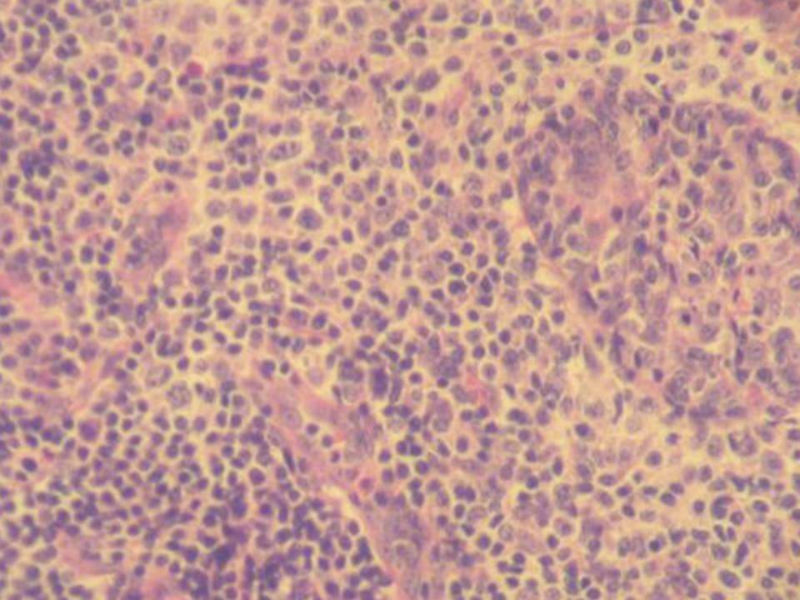

腮腺肿物:良性淋巴上皮病变(Mikulicz病)

女,71岁,腮腺肿物,临床诊断混合瘤。